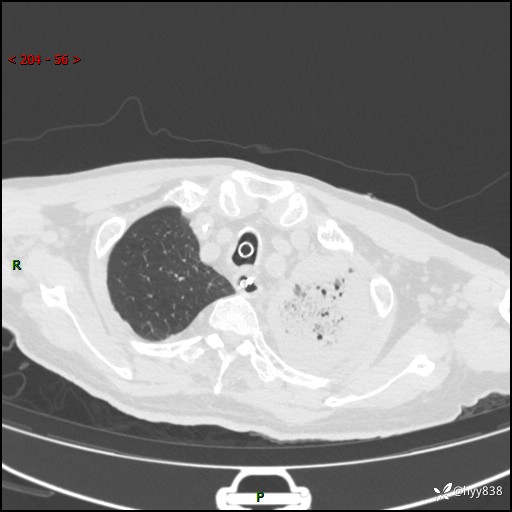

胸部CT复查(2024.8.5)